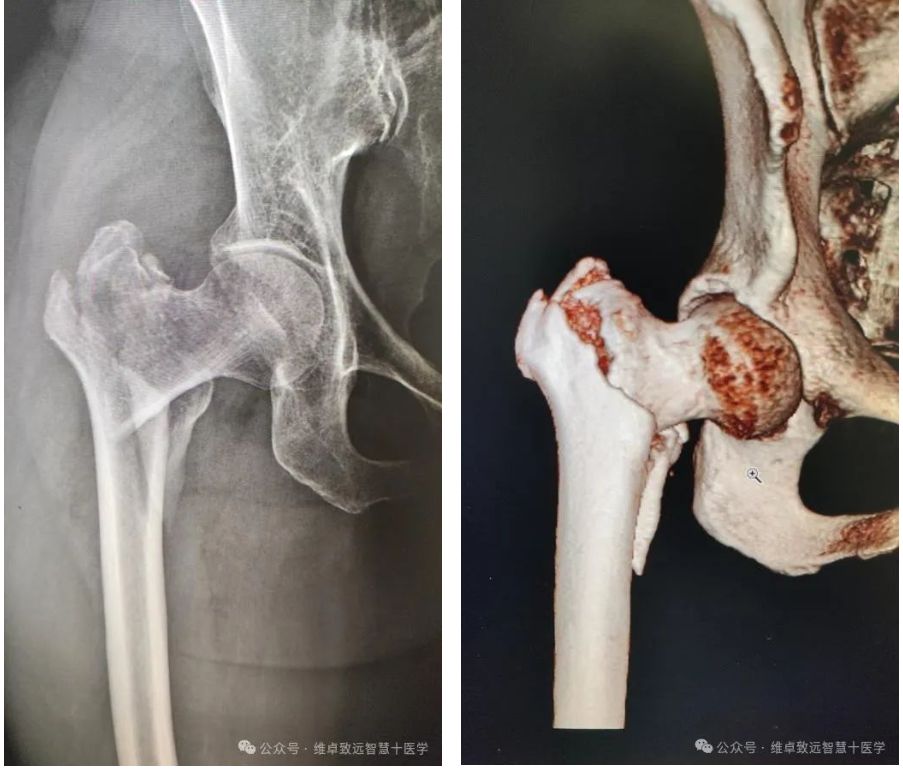

据悉,此次手术的患者为61岁女性,因不慎摔倒,感觉右腕部、右髋部疼痛明显,无法站立及行走,无明显头晕、恶心、呕吐等症状。就诊于解放军总医院海南医院外院行X光片检查,显示右侧桡骨远端骨折、右侧股骨粗隆间骨折。

患者X光片及三维重建